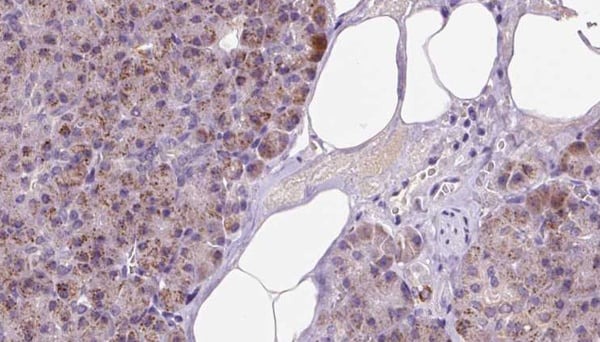

IHC (Immunohiostchemistry)

(AAA323218 at 1/100 staining Human pancreas cancer tissue by IHC-P. The sample was formaldehyde fixed and a heat mediated antigen retrieval step in citrate buffer was performed. The sample was then blocked and incubated with the antibody for 1.5 hours at 22 degree C. An HRP conjugated goat anti-rabbit antibody was used as the secondary.)